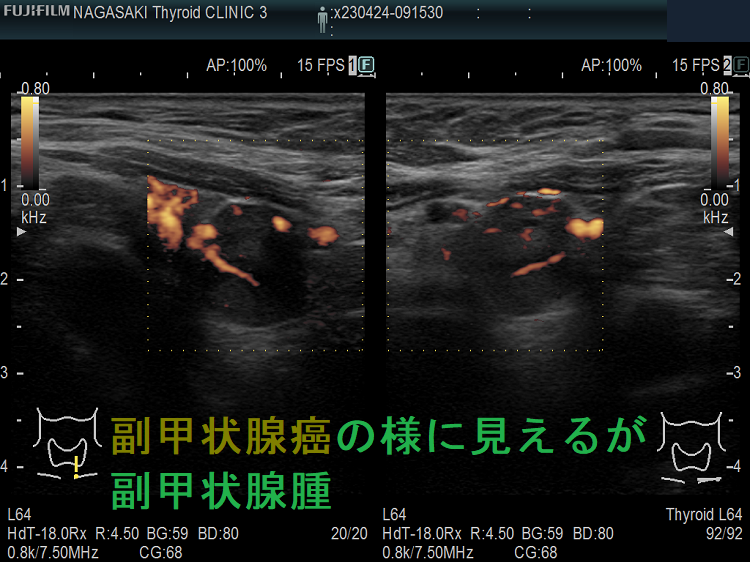

甲状腺内副甲状腺腫は、超音波(エコー)検査で甲状腺腫瘍と形態的に鑑別できない場合があります(実際は下の写真のように診断できていますが・・)。特徴的な超音波(エコー)所見は、腹側の高エコーで感度86%、特異度100%です[Surgery. 2012 Dec;152(6):1193-200.]。さらに、99m-Tc MIBIシンチグラフィーで取り込み(集積)があれば甲状腺内副甲状腺腫と診断できます。

99m-Tc MIBIを取り込まない甲状腺内副甲状腺腫もあるため、穿刺細胞診を行い、針先洗浄液でインタクトPTHを測定(FNA-PTH)。甲状腺内副甲状腺腫は、甲状腺が周囲にあるため、針に沿った副甲状腺細胞のばらまき(播種)・出血の危険が少なくなります。

腺腫様甲状腺腫に合併する甲状腺内副甲状腺腫

腺腫様甲状腺腫に合併する甲状腺内副甲状腺腫は、腺腫様結節と鑑別が難しいだけでなく、多腺性(5-6腺)のケースがあります。